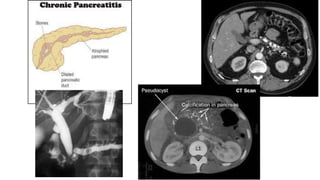

Chronic pancreatitis is a rare disease that mainly affects males around age 40, with symptoms present for 3-10 years on average before diagnosis. It is commonly caused by alcohol, recurrent pancreatitis, autoimmune or genetic factors. Symptoms include abdominal pain, nausea, poor appetite and weight loss. Complications can include pseudocysts, pancreatic duct strictures, stones, bile duct obstruction, maldigestion, diabetes, and pancreatic cancer in some cases. Diagnosis involves imaging like ultrasound, CT, MRI, and EUS along with tests of fecal fat and elastase levels.